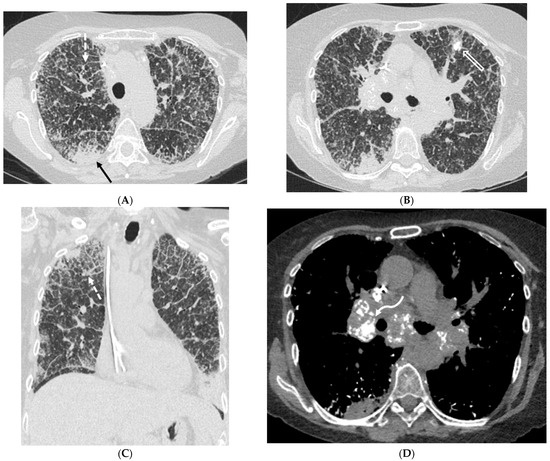

6.2. Pulmonary Alveolar Proteinosis (PAP)

- Frazier, A.A.; Franks, T.J.; Cooke, E.O.; Mohammed, T.-L.H.; Pugatch, R.D.; Galvin, J.R. From the archives of the AFIP: Pulmonary alveolar proteinosis. Radiographics 2008, 28, 883–899. [Google Scholar] [CrossRef] [PubMed]

- Murch, C.; Carr, D. Computed tomography appearances of pulmonary alveolar proteinosis. Clin. Radiol. 1989, 40, 240–243. [Google Scholar] [CrossRef]

- Prakash, U.B.; Barham, S.S.; Carpenter, H.A.; Dines, D.E.; Marsh, H.M. Pulmonary alveolar phospholipoproteinosis: Experience with 34 cases and a review. Mayo Clin. Proc. 1987, 62, 499–518. [Google Scholar] [CrossRef]

| Pulmonary alveolar proteinosis (PAP) | smooth | + | ++ | + | − | − | − | +/− | − | − |